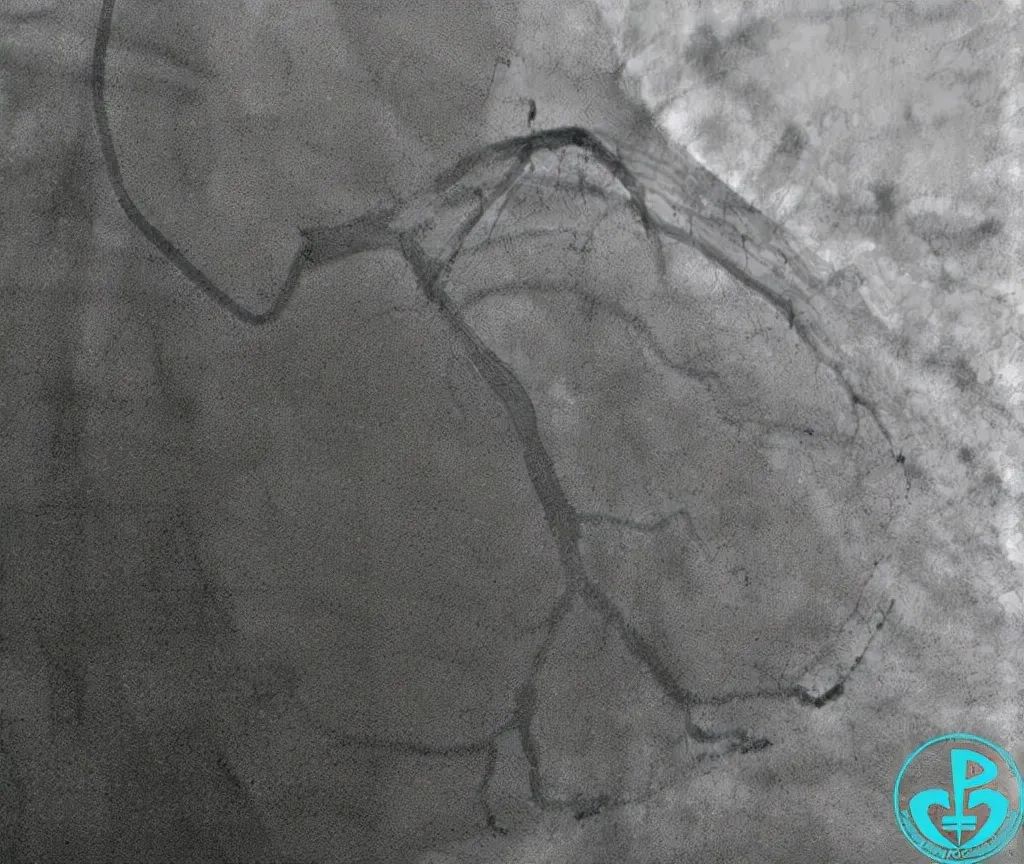

图源:金道医学进行介入手术期间,患者植入支架后,影像显示支架定位准确,血路通畅。同时,患者的胸痛症状减轻,于是便返回病房。

其实,患者的死亡本是可以避免的。刘鸣医生表示,患者属于前降支近段的急性病变,回旋支一定要放导丝,甚至预留球囊。患者死因是血栓脱落,导致回旋支选段和OM急性闭塞,在放完支架后,依然可以看到血栓影。

但当时医生的注意力都在前降支,忽略了回旋支,所以没能及时发现和处理。对于这一结局,刘鸣医生替病人感到惋惜!